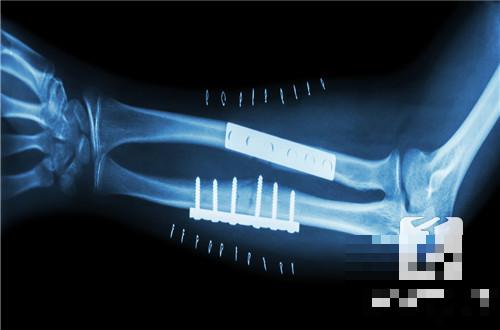

2、内植物失败

如果出现了断板断钉、严重感染等情况,医生往往会考虑取出内固定物。除了断裂和感染,还有一种极端情况:内植物跑偏到其它部位,曾经有个病人做脊柱手术,内固定竟然游走到了胸腔里!这种一生不羁放纵爱自由就必须要被采取措施了。